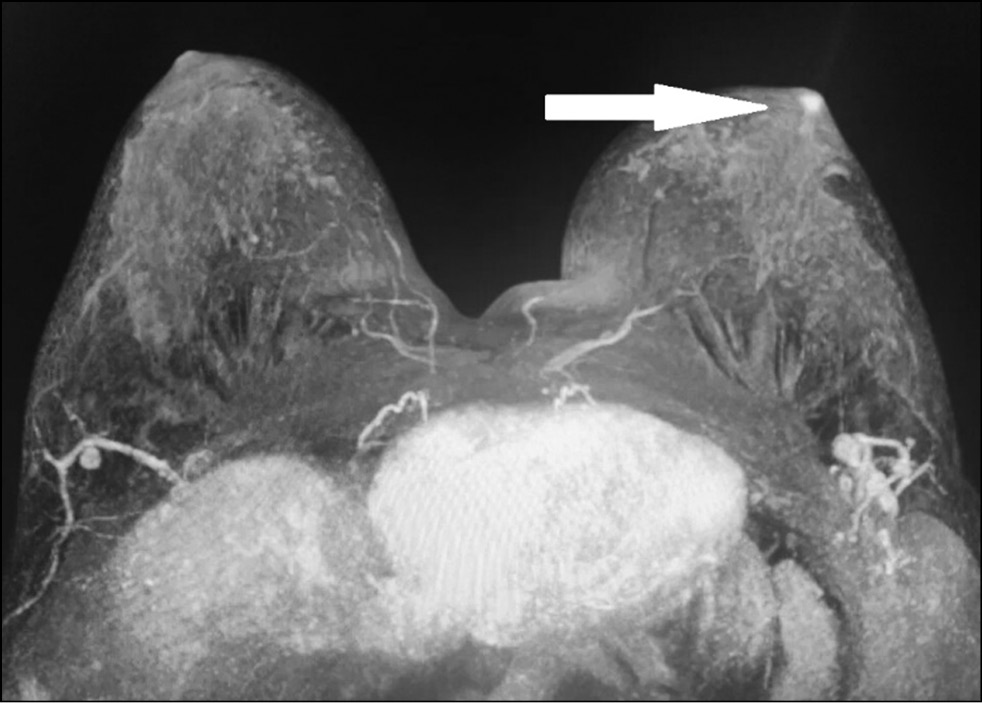

In a 43-year-old patient who had no complaints, the breast was examined by MRI to assess the integrity of implants. The asymmetric enhancement of the left nipple was accidentally found (Figs. 9 and 10). Three-year dynamic observation did not reveal any unfavorable changes.

Figure 9. Magnetic resonance imaging (early postcontrast series): asymmetric contrast accumulation in the left nipple; normal finding (arrow).

Figure 10. Magnetic resonance imaging (MIP): asymmetric contrast accumulation in the left nipple; normal finding (arrow).